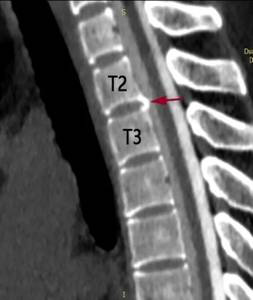

宋先生的脊柱磁共振检查可见第2、3胸椎之间有“骨刺”形成(红箭头)刺破硬脊髓膜,造成脑脊液外漏(蓝箭头)医院供图